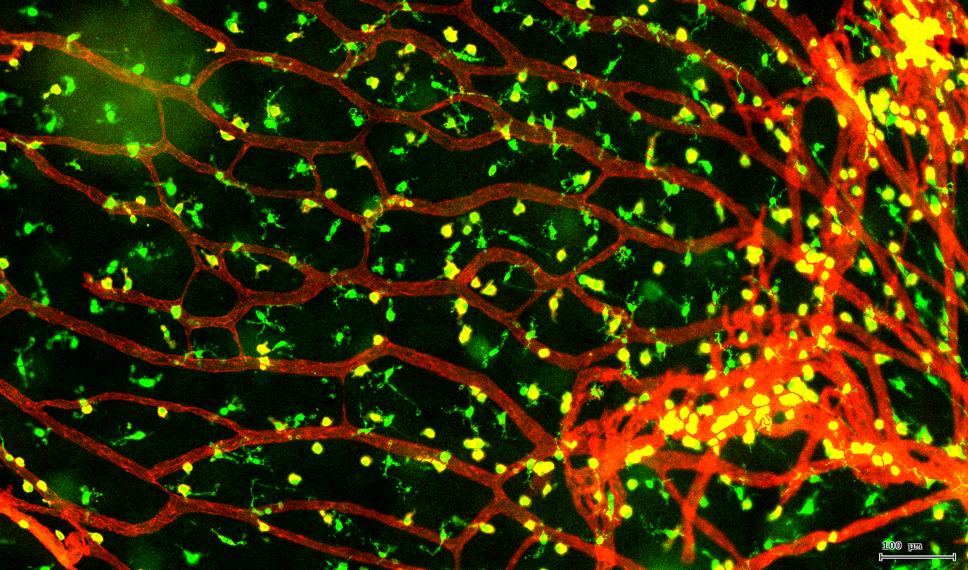

视网膜荧光样本中小胶质细胞胞体、神经纤维识别、血管识别、血管斑点识别、神经元与血管的距离分析。

7. 根据毛细血管亮斑的识别结果,统计新生小血管数量。

血管识别:根据Texa Red通道进行识别,并去除面积小的及非同一焦面的血管,仅对确定的清晰的同一焦面的大血管进行面积统计。

血管与小胶质细胞的距离0-0.1μm(红色框线标记)

血管与小胶质细胞的距离0.1-1μm(粉色标记)

血管与小胶质细胞的距离1-3μm(粉色标记)